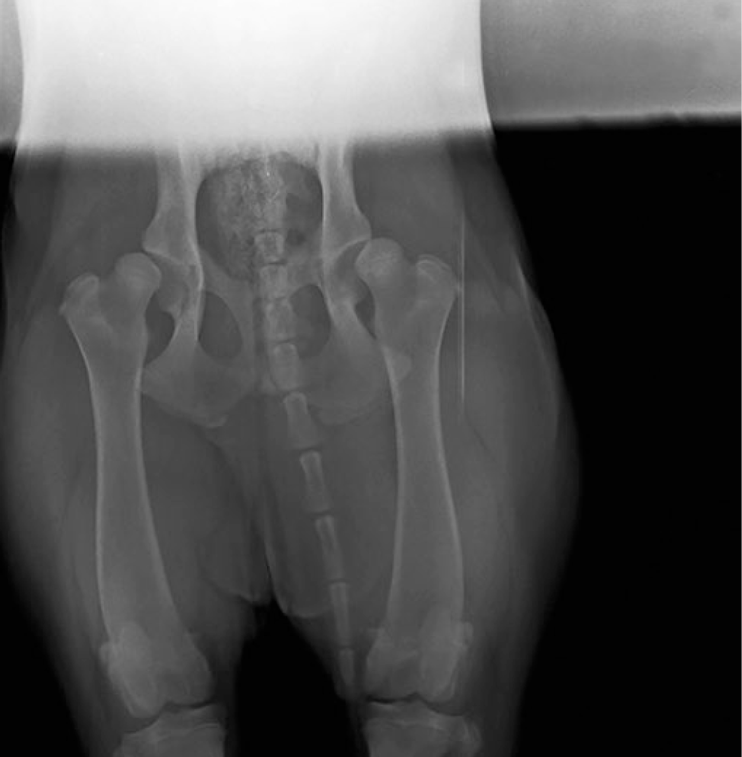

Рис.4. До операции: вывих правого ТБС на фоне дисплазии, подвывих левого ТБС на фоне дисплазии.